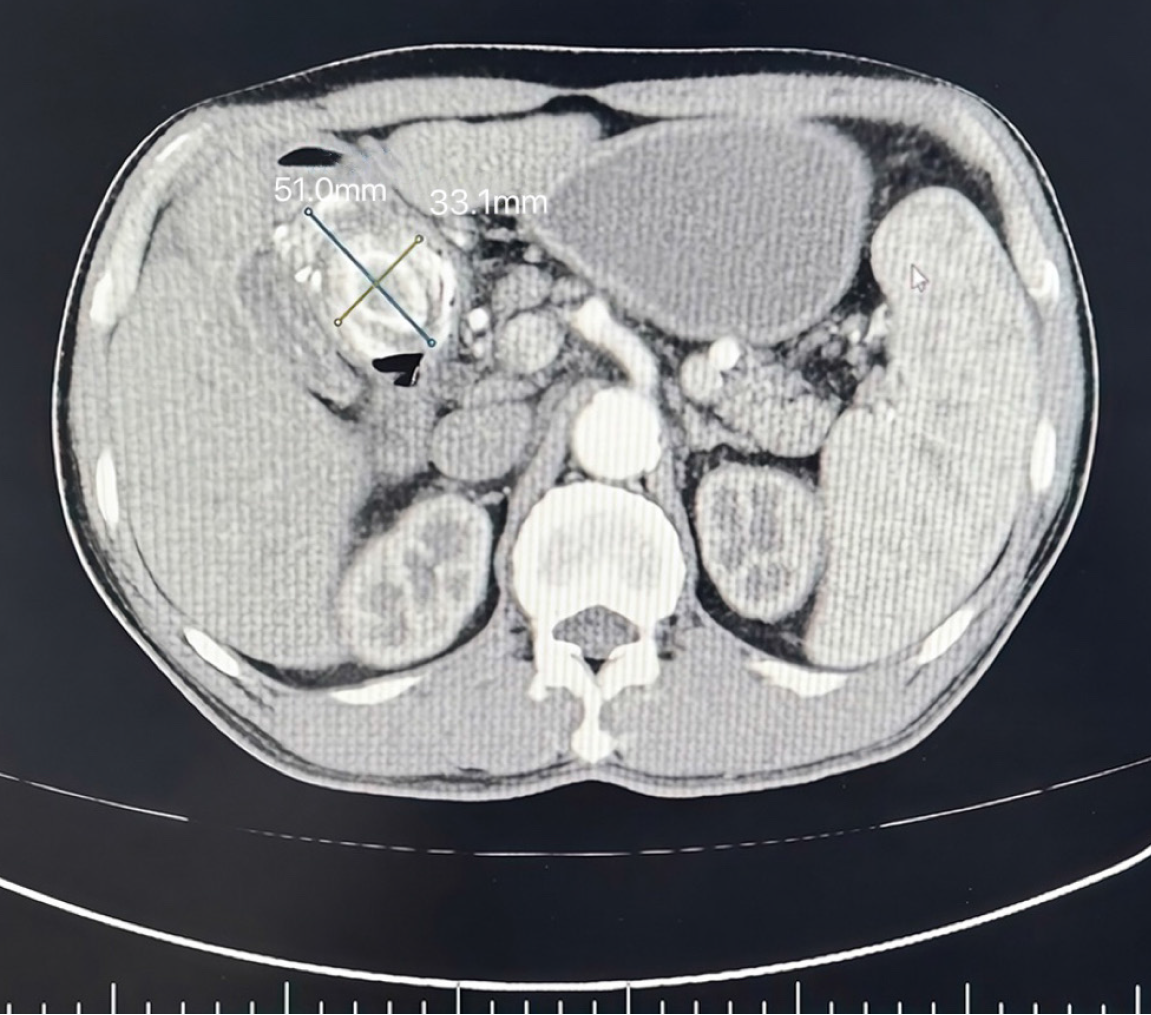

The surgical procedure was successful. Considering the prolonged duration of the biliary and intestinal interventions and severe intra-abdominal infection, the patient received comprehensive postoperative management, including fasting, intravenous antibiotic therapy, parenteral nutrition, and acid-suppressive treatment for gastric mucosal protection. On postoperative day 3, follow-up abdominal CT imaging revealed mild changes indicative of fluid leakage at the surgical site, albeit no significant abnormalities (Figure 3). The nasogastric and abdominal drainage tubes remained patent and functioned well, showing effective drainage. By postoperative day 8, enteral nutrition was initiated gradually. On postoperative day 20, the patient showed good tolerance to a liquid diet without any adverse symptoms. As the left abdominal drainage tube displayed no further output, it was subsequently removed. On postoperative day 23, the nasogastric tube was removed, and the patient reported no discomfort following its removal. A second follow-up CT scan performed on postoperative day 27 exhibited no notable abnormalities (Figure 4). The right-sided abdominal drainage tube was removed, and the patient was discharged on postoperative day 30. During his stay, no postoperative complications such as biliary or enteric fistula, gastrointestinal bleeding, or gastroparesis were observed. Histopathological examination of the excised gallbladder confirmed chronic cholecystitis, with localized areas of hemorrhage and necrosis of the gallbladder wall, along with the presence of mixed gallstones (Figure 5). The patient underwent structured follow-up every 6 months for 2 years postoperatively, including abdominal ultrasonography and hepatic function assessments. To reduce the risk of recurrence, a low-fat diet of < 40 g of fat per day was advised, along with an annual CT scan to evaluate the structural integrity of the repaired duodenal region. At the follow-up after 2 years of his discharge, the patient remained clinically stable. No abnormalities were detected in liver function tests, complete blood count, or other routine laboratory parameters. Abdominal CT imaging also demonstrated satisfactory recovery of the operative site, with no signs of recurrence or complications (Figure 6).

Figure 6

Figure 6  Two years after discharge (April 21, 2024), the abdominal computed tomography scan showed good recovery in the surgical area.